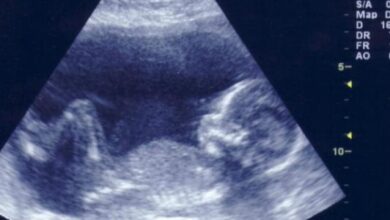

تعتمد الطّريقة المستخدمة للإجهاض على مدّة حدوث الحمل وتقدّمه، لكن يُنصح بإجراء تصويرٍ بالموجات فوق الصّوتيّة قبل إجراء الإجهاض للتّأكد من أنّ الجنين في مكانه الصّحيح (ليس خارجاً من الرّحم)، وللتّأكد من مدّة الحمل بشكلٍ دقيقٍ أيضاً.[٢]